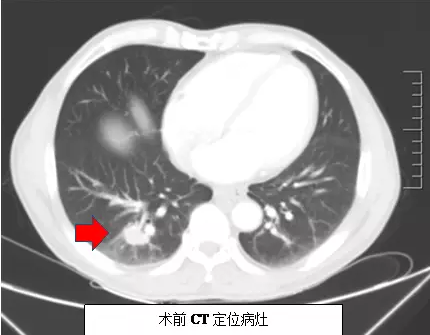

患者姜某因消化道出血在介入科住院时发现右下肺小病灶,经该科肺占位穿刺活检后确诊为支气管肺泡癌。由于患者基础疾病较多并已有腋窝淋巴结转移,外科开胸手术风险极高,且家属不愿行外科手术经。科主任吕军及科内会诊后,决定为患者采用CT引导下肺部肿瘤射频消融治疗。患者射频治疗后复查发现病灶完全消融,肺内无明显出血及气胸,无明显不良反应,疗效非常好,术后第二天患者已能正常活动。